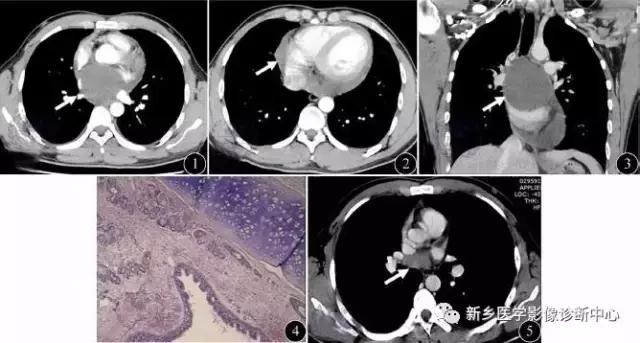

肺A-V瘘

无症状或有咯血,局部胸壁可闻及血管杂音,好发于肺下叶。圆形或椭圆形肿块或轻度分叶,边缘清楚,密度常混杂,可有点状钙化,增强时可见迂曲血管影,并可显示供血动脉。

包虫囊肿

好发于肺中下野,继发感染时有发热,咳嗽胸痛,常见于牧区。圆形密度增高影,边缘清楚,内为水样密度,“水上浮莲征”为特征表现。

左图:右肺上叶小的破裂包虫囊肿,塌陷的棘球蚴包膜“水上浮莲征”

右图:充满整个右半胸腔巨大包虫囊肿。